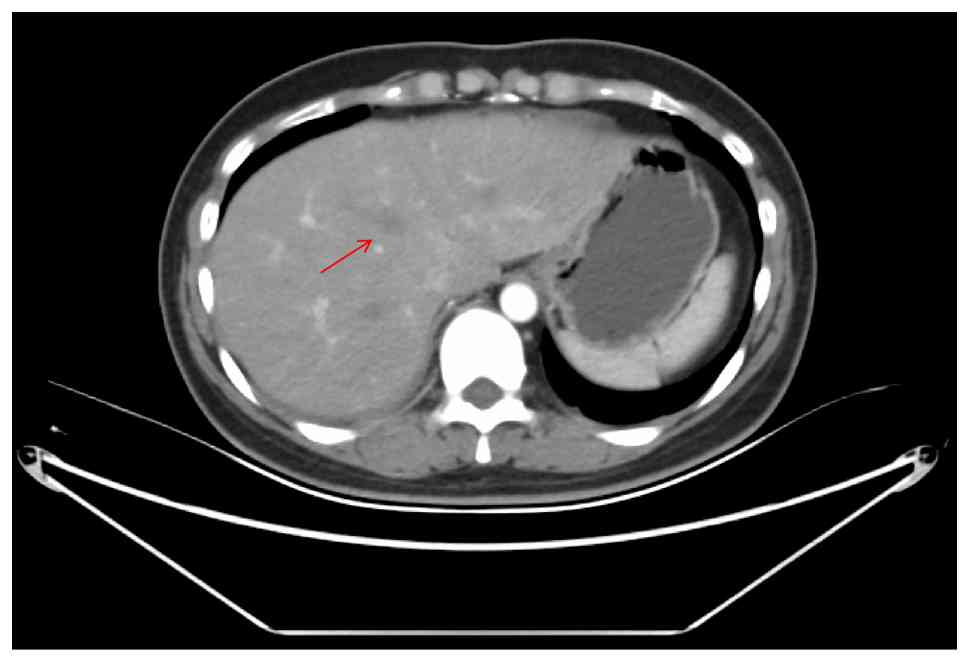

As early as the chest CT scan in January 2024, a soft-tissue mass measuring 3.2×2.5 cm was detected in the lower lobe of the right lung (Fig. 2A and D). However, CT scans of the chest in December 2024 (size, 10×8.4×5.6 cm; Fig. 2C and F) showed that the malignant space in the lower lobe of the right lung was markedly enlarged compared with the previous scan in October 2024 (size, 5.2×3.5 cm; Fig. 2B and E), with multiple ground-glass density nodules of varying sizes in both lungs (the largest diameter of which was ~1.1 cm), multiple enlarged lymph nodes in the right hilar and mediastinal regions, and occlusion of the right lower lung bronchus with obstructive inflammation, as well as thickening of the right lower pleural membrane. Bone destruction of the seventh thoracic vertebra with pathological fracture suggested bone metastasis. CT scans of the abdomen cavity (Fig. 3) showed multiple new lesions in the liver (the largest of which was ~2.7 cm in diameter), suggesting metastases. The imaging suggested that the condition of the patient was in a deteriorating state.

CT scan of the patient's abdomen. A

round low-density shadow was seen in the liver, which was a new

lesion, and a metastatic tumor was considered. The red arrow points

to one of the lesions.

Figure 3.

CT scan of the patient's abdomen. A round low-density shadow was seen in the liver, which was a new lesion, and a metastatic tumor was considered. The red arrow points to one of the lesions.